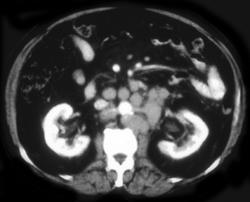

Virtual Colonoscopy With Volume Rendering